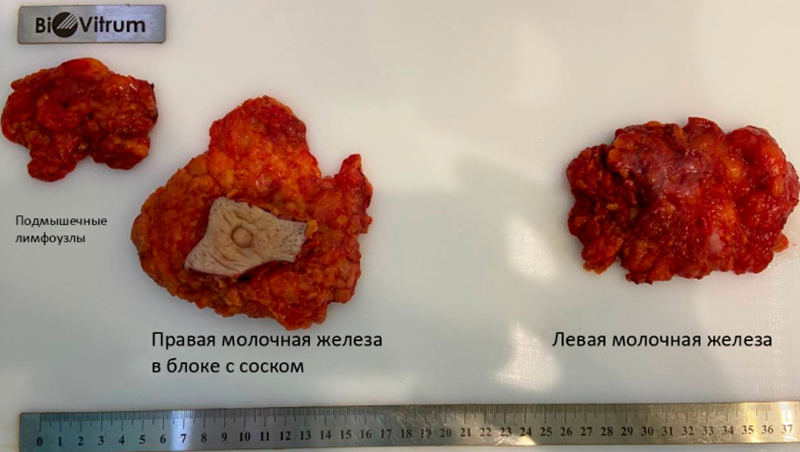

В таких случаях на первом этапе лечение начинают с операции. Мы остановились на подкожной двусторонней мастэктомии (когда удаляют железу без удаления кожи) с одномоментным эндопротезированием имплантами. В ее случае мы поставили полиуретановые импланты по 265 мл. Для того что бы понять нужна ли ей будет лучевая терапия мы выполнили удаление поверхностной группы подмышечных лимфоузлов (отек руки в таких случаях не развивается). Операция 2 часа, кровопотери нет. Первая перевязка будет на 3й ил 4й день. Пациентка готовиться к выписке.

В таких случаях на первом этапе лечение начинают с операции. Мы остановились на подкожной двусторонней мастэктомии (когда удаляют железу без удаления кожи) с одномоментным эндопротезированием имплантами. В ее случае мы поставили полиуретановые импланты по 265 мл. Для того что бы понять нужна ли ей будет лучевая терапия мы выполнили удаление поверхностной группы подмышечных лимфоузлов (отек руки в таких случаях не развивается). Операция 2 часа, кровопотери нет. Первая перевязка будет на 3й ил 4й день. Пациентка готовиться к выписке.